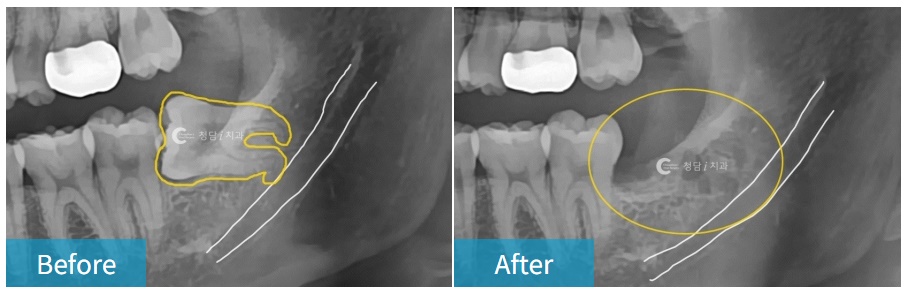

매복 사랑니, 신경과 가깝거나 엑스레이에 중첩되어 보이는 사랑니,

뿌리가 휘어있는 사랑니, 거꾸로 누워있는 사랑니 등

“턱 신경과 가까이 있는 오래된 매복 사랑니 발치했어요.

치조골의 구조, 신경관 위치, 치아의 각도 등을 정확히 파악하고,

주변의 뼈 손상을 최소화하며 빠르게 뽑아야 환자의 고통을 줄일 수 있기 때문에

내원하시면 X-ray와 CT 촬영 후 신경과의 거리, 뿌리의 방향 등을 분석한 후 발치를 진행하게 됩니다.